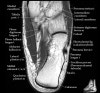

- Axial section

Axial PD fat suppression evaluates the tendons and ligaments of the ankle particularly after acute/subacute injuries. It also is sensitive to talar dome osteochondral defects. Alternatively, a T2 sequence can be used to eliminate magic angle artifact that may occur as the tendons travel around the malleolar turns.

Tibiofibular ligaments

Lateral ankle ligaments

Deltoid and spling ligaments

Tendon(Achilles, Medial, Lateral, Anterior)